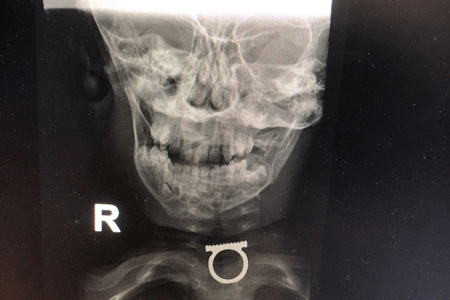

An x-ray of a two-year-old boy with a ring stuck in his throat. Photo by Shaarei Zedek spokesperson

The parents, residents of the eastern Jerusalem neighbourhood of Shuafat, immediately took the boy to a local clinic, where an X-ray showed the ring was stuck in the boy’s throat. Clinic staff sent the family to Shaare Zedek to have the ring removed. Although the boy was not having difficulty breathing, the staff worried that the ring’s jagged edges might damage the esophagus.